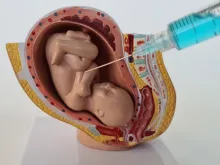

Projeto de Lei propõe proibir cloreto de potássio em abortos tardios previstos em lei

Tramita na Câmara do Deputados um projeto de lei que veta o procedimento de assistolia fetal em casos de aborto... Leia mais